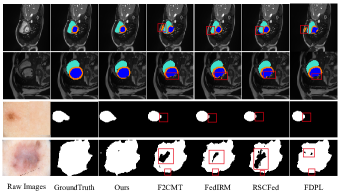

Visual Comparisons:

We visualize the segmentation results of different methods on ACDC and ISIC dataset in Figure 4. Some methods with better performance are chosen including F2CMT, FedIRM, RSCFed and FDPL. The two cases above are the results of the segmentation on ACDC dataset while the two cases below are the results on ISIC dataset. The green, orange and blue regions denote the right ventricle, myocardium and left ventricle in cardiac MRI images. In the first case, there are all some false positives (red box) appeared in the segmentation results of four compared methods. However, our method has no false positives and possesses higher overlap ratio. In the remaining cases, the segmentation results own many false negatives (red box) compared with the GroundTruth. As for the result of our method, the false negatives are fewer and more details are preserved. These experimental results illustrate the effectiveness, robustness and generalization of our proposed method.